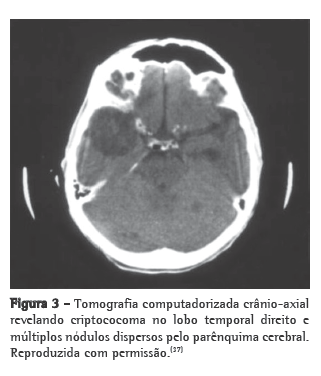

A criptococose pulmonar isolada (sem metástase cerebral) ou com massa cerebral (com metástase cerebral) causada por C. gattii pode clínica e radiologicamente simular câncer de pulmão (Figuras 2 e 3).(37) Tem sido descritos casos de consolidação do lobo superior com apresentação típica de síndrome de Pancoast.(38)